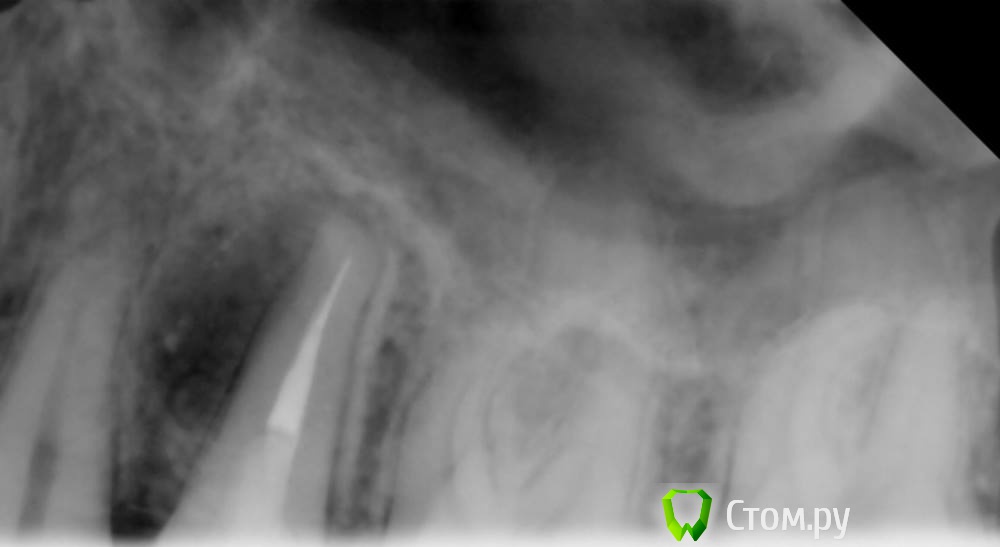

Юлия Арт Опубликовано 13 марта, 2014 Поделиться Опубликовано 13 марта, 2014 Здравствуйте! я совершенно в растерянности...около месяца назад мне сделали снимок верхних коренных, и врач увидел там большое воспаление-кисту у пятого зуба. сказал что она находится вбоку, а зуб депульпирован, возможно, с трещиной и надо удалять...месяц я себя настраивала, сделала - таки запись в госпиталь к хирургу, и сегодня там была... Хирург отправил меня на панорамный снимок, посмотрел и сказал не понимает почему меня к нему на удаление зуба послали - воспаления, говорит, нет, зуб нормальный, иди домой...я в шоке до сих пор-что это было?выкладываю фото " с кистой" в феврале и фото сегодня всей челюсти. Пожалуйста, прокомментируйте Ссылка на комментарий

Гарриевич Опубликовано 13 марта, 2014 Поделиться Опубликовано 13 марта, 2014 (изменено) мое мнение такое, очаг разрежения рисунка костной ткани в области 2.5 зуба с медиальной стороны есть. Зуб нужно перелечивать под микроскопом для того, чтобы запломбировать это боковое ответвление. Удалять зуб не надоPS на ОПТГ таких таких очагов может быть не видно, в следствии наложения позвонков, ключиц, сережек и пр. Изменено 13 марта, 2014 пользователем Гарриевич Ссылка на комментарий

Mane Опубликовано 13 марта, 2014 Поделиться Опубликовано 13 марта, 2014 На прицельном снимке виден воспалительный процесс. На понарамном - нет. "Киста" никуда не делась. Просто на панорамном снимке ее не видно. Такой снимок. Нужно сделать КТ (компьютерную томографию) и дать нам посмотреть. Мы и определим возможную причину. Если болит- решайте вопрос быстрее. Если трещина/фрактура корня - зуб на удаление. Если просто пропустили канал- перелечиваете и все будет хорошо. 2 Ссылка на комментарий